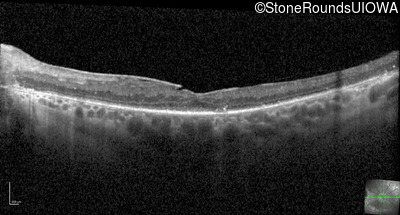

Optical Coherence Tomography - Right - 20/80 +1

Exemplar / OCT Stack

OCT Stack